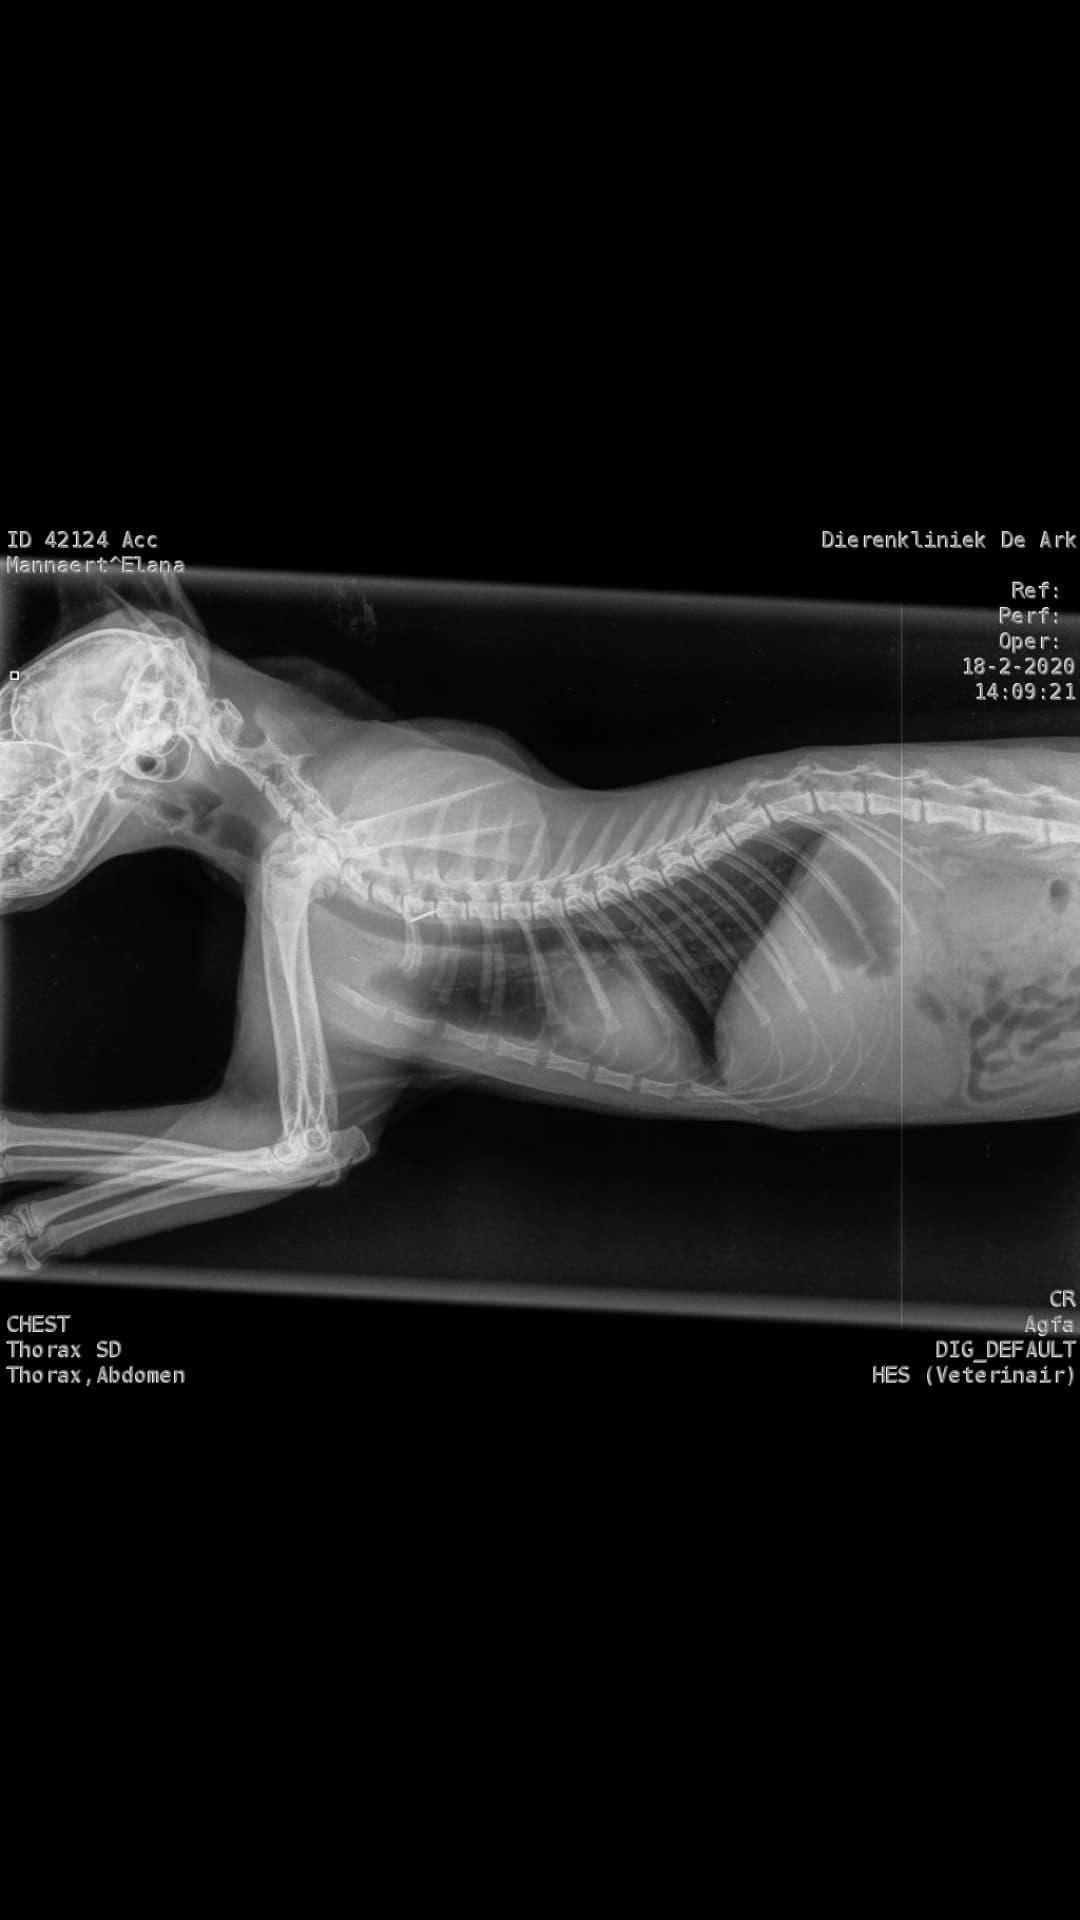

Tuesday, February 18, 2020 - 84 25 39 degrees measured at the vet. The blood tests already show that the values have changed enormously and are cause for great concern. Elana has also been fully checked. A possible accident is ruled out by means of X-rays. Her A/G values have now dropped to 0.57, this was 1.13 on day 82 of the treatment